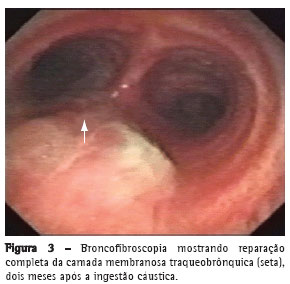

A radiografia de tórax de controle, após a endoscopia digestiva alta, revelou pneumotórax esquerdo. Foi realizada drenagem torácica esquerda com imediata reexpansão pulmonar. Na broncofibroscopia

observou-se área de destruição da traquéia distal, carina e brônquio esquerdo de aproximadamente 3 x 1,5 cm (Figuras 2 e 3), exposição de

tecido mediastinal, desepitelização e retração de epiglote e corda vocal direita.

O paciente apresentou evolução positiva, recebendo alta hospitalar dezessete dias após sua admissão. Dois meses após a alta, apresentava dispnéia progressiva nos últimos dez dias, tinha intensa

cornagem e tiragem intercostal. A broncofibroscopia mostrou uma estenose supraglótica (neoformação anular de tecido fibrótico) sendo indicada a traqueostomia. Foi mantido em acompanhamento